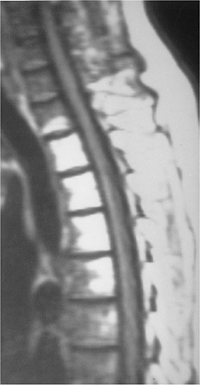

FIGURE 12-7 Gaucher disease. Coronal T1-weighted images of the knees (A) and sagittal T1-weighted images of the spine (B) showing low signal intensity throughout the marrow.